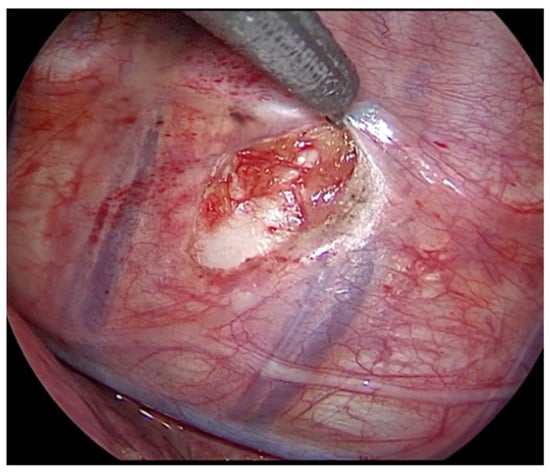

2.2.2. Surgical Technique